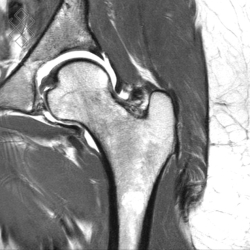

Arthro-IRM de la Hanche

La durée de l'examen est d'environ 20 minutes. Pour repérer la zone souahitée, le radiologue fera une scopie. Ensuite, il effectuera une désinfection puis une anesthésie locale. Pour l'injection du produit de contraste à base de gadolinium, il introduira une aiguille dans la zone repérée, puis il appliquera un pansement étanche. Enfin, vous serez installés afin d'effectuer l'IRM de la hanche.